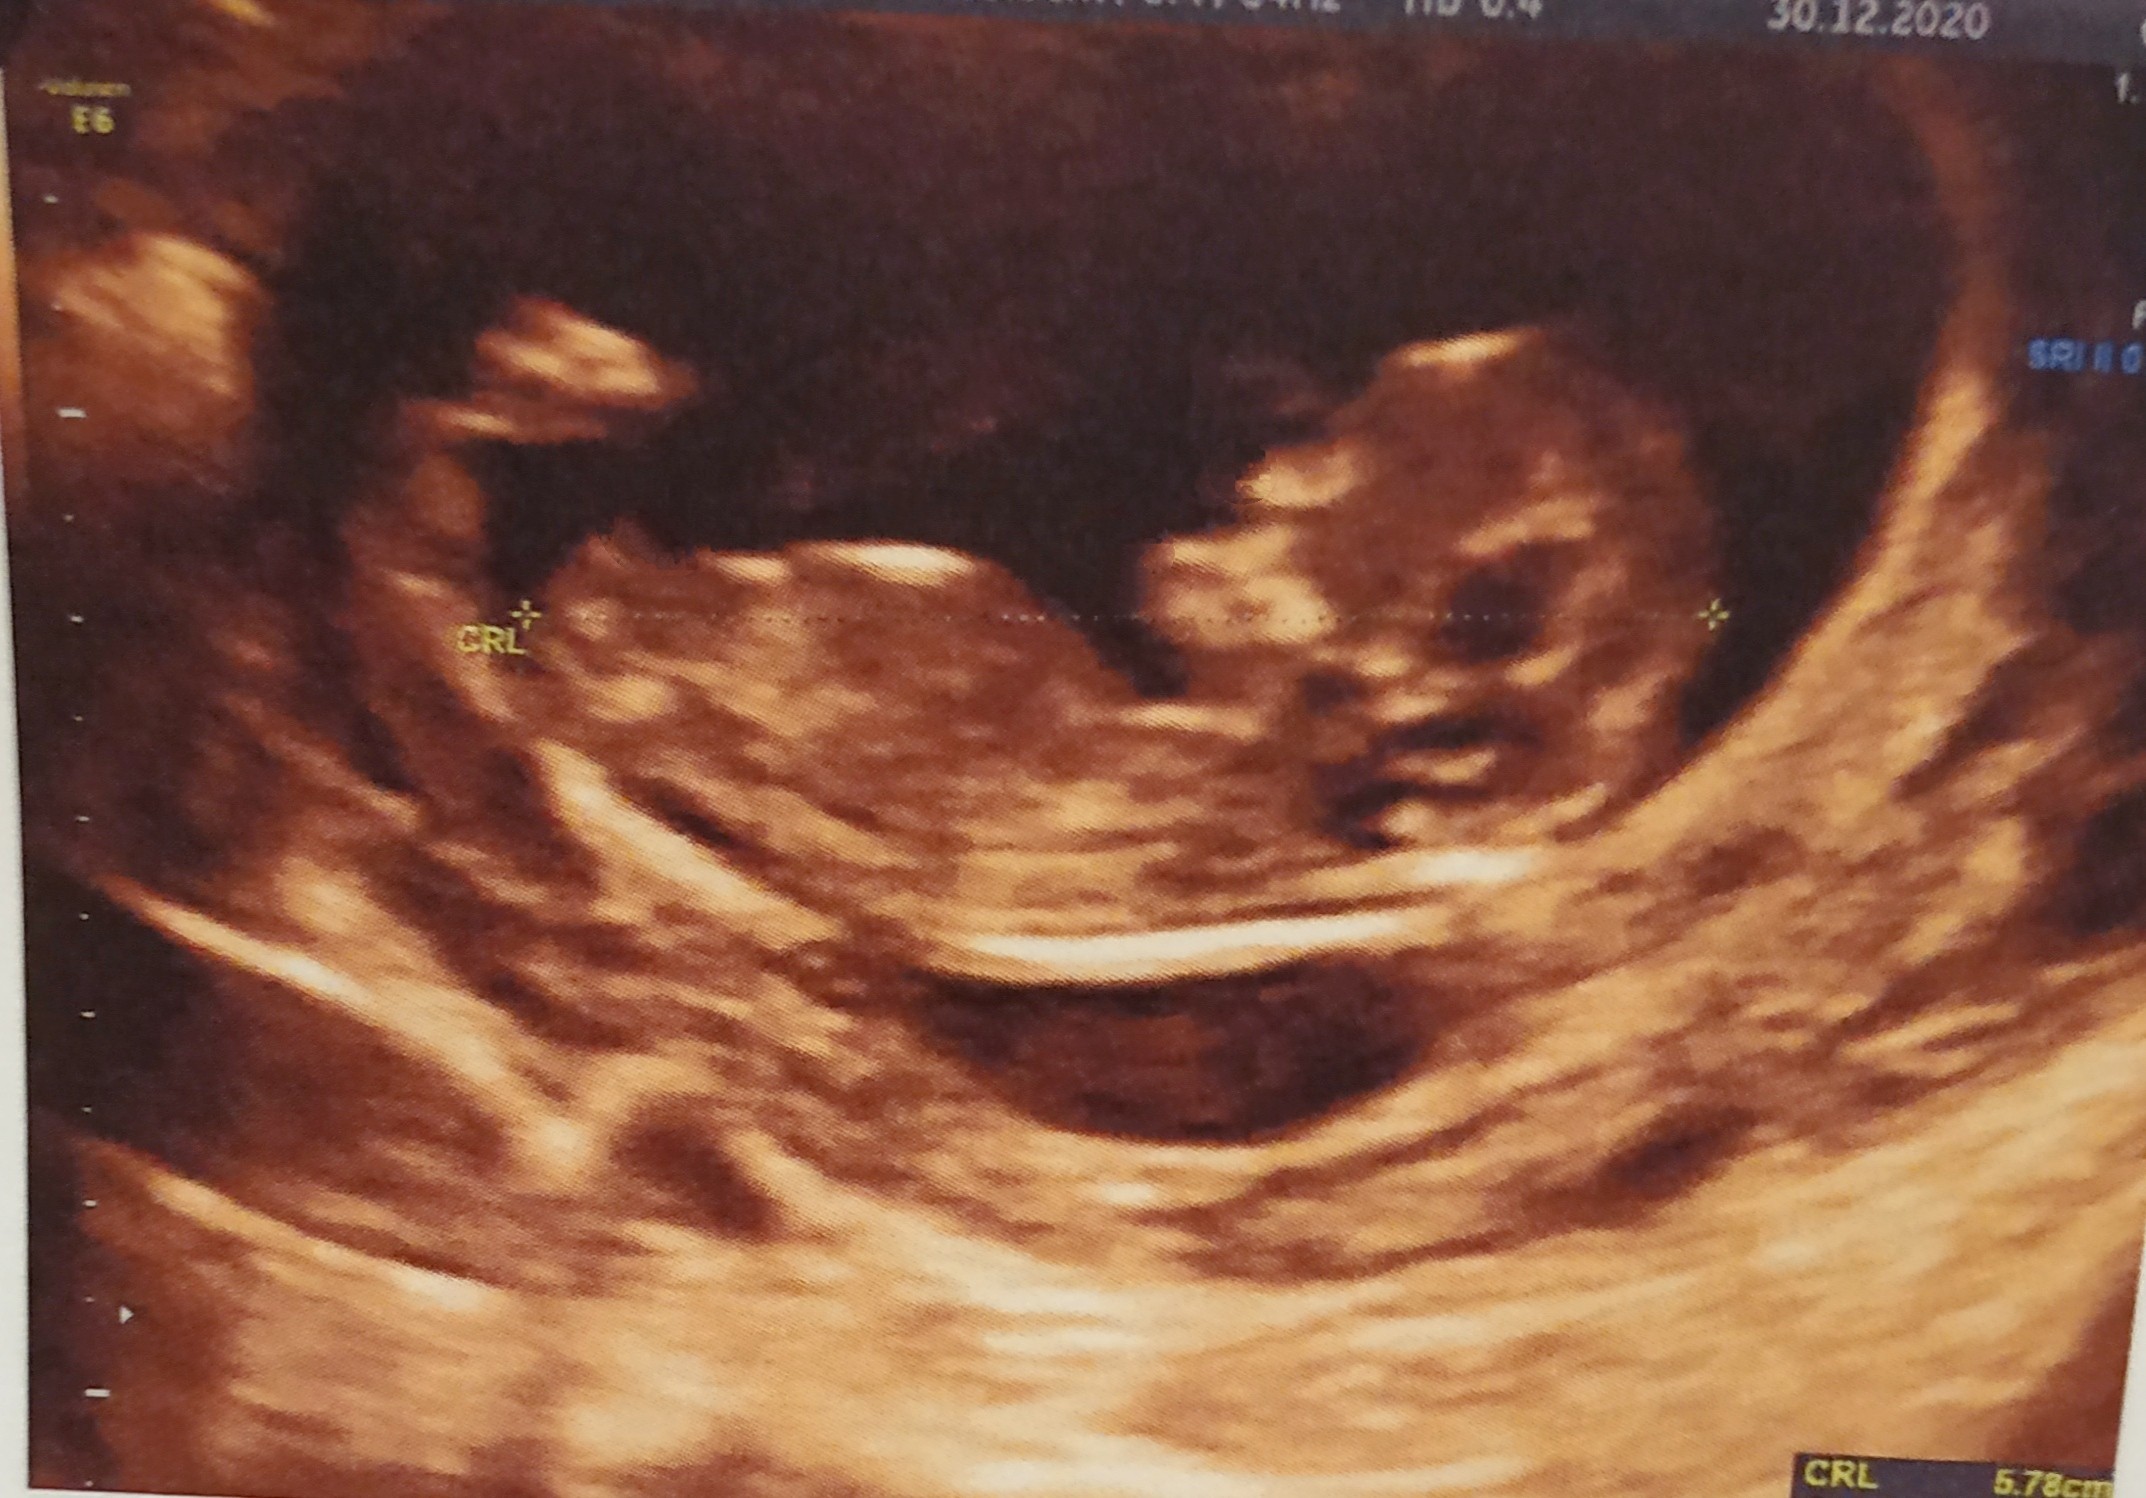

Zdjęcie nie jest tak wyraźne jak u Pani wyżej , ale chyba też skłaniałbym się ku dziewczynce.